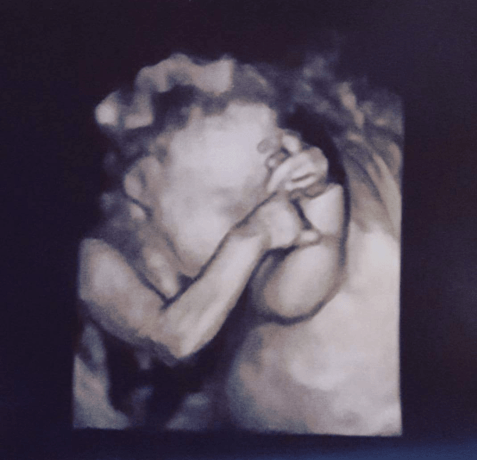

During the ultrasound at my 27-week appointment, I watched as the team took more pictures of Tessa’s little heart and organs. Each ultrasound appointment became a blessing, a chance to see my daughter moving and kicking as her image popped up on the dark screen.

“She is still fighting. Each appointment I hold my breath before I hear or see her heartbeat, even if I have just felt her kicking moments before. I am getting to the point where I wonder, ‘Is this the last time I’m going to see her on the screen? Is this the last time I will hear her heartbeat?’ As emotional as that is, it is also that much more special to me that I get to hear or see her, and I cherish that sound of thumping beats, and try to hold still that moment that I can see her covering her face like her sister did during her ultrasounds.